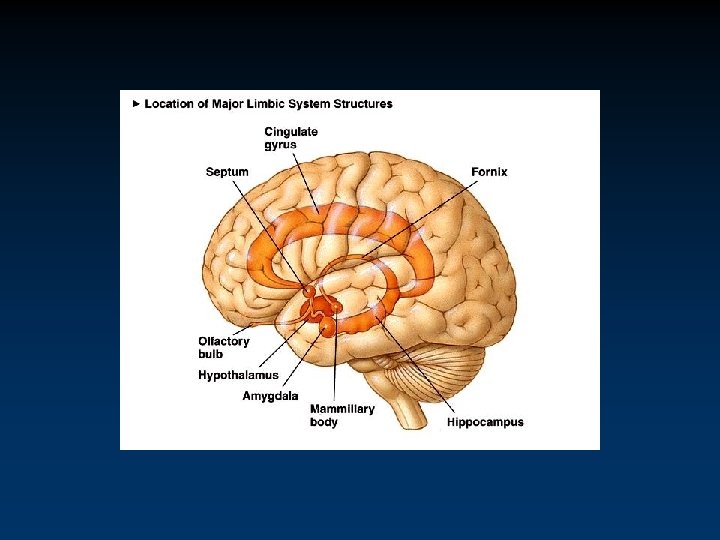

Two Limbic Circuits Anterior Thalamus Cingulate Gyrus Dorsomedial Thalamus Mamillothalamic Tract Mammilary Bodies Fornix Hippocampus Medial (Papez) Orbitofrontal Amygdalofugal pathways Uncus Amygdala Lateral

Two Limbic Circuits and the Two-system theory of amnesia Anterior Thalamus Cingulate Gyrus Dorsomedial Thalamus Mamillothalamic Tract Mammilary Bodies Orbitofrontal Amygdalofugal pathways Fornix Uncus Hippocampus Amygdala PRPH Medial (Papez) Lateral

Two Limbic Circuits and the Two-system theory of amnesia Anterior Thalamus Cingulate Gyrus Dorsomedial Thalamus Mamillothalamic Tract Mammilary Bodies Fornix Hippocampus Medial (Papez) Orbitofrontal Amygdalofugal pathways Uncus Amygdala Lateral

Two Limbic Circuits Anterior Thalamus Cingulate Gyrus Dorsomedial Thalamus Mamillothalamic Tract Mammilary Bodies Fornix Hippocampus Medial (Papez) Orbitofrontal Amygdalofugal pathways Uncus Amygdala Lateral